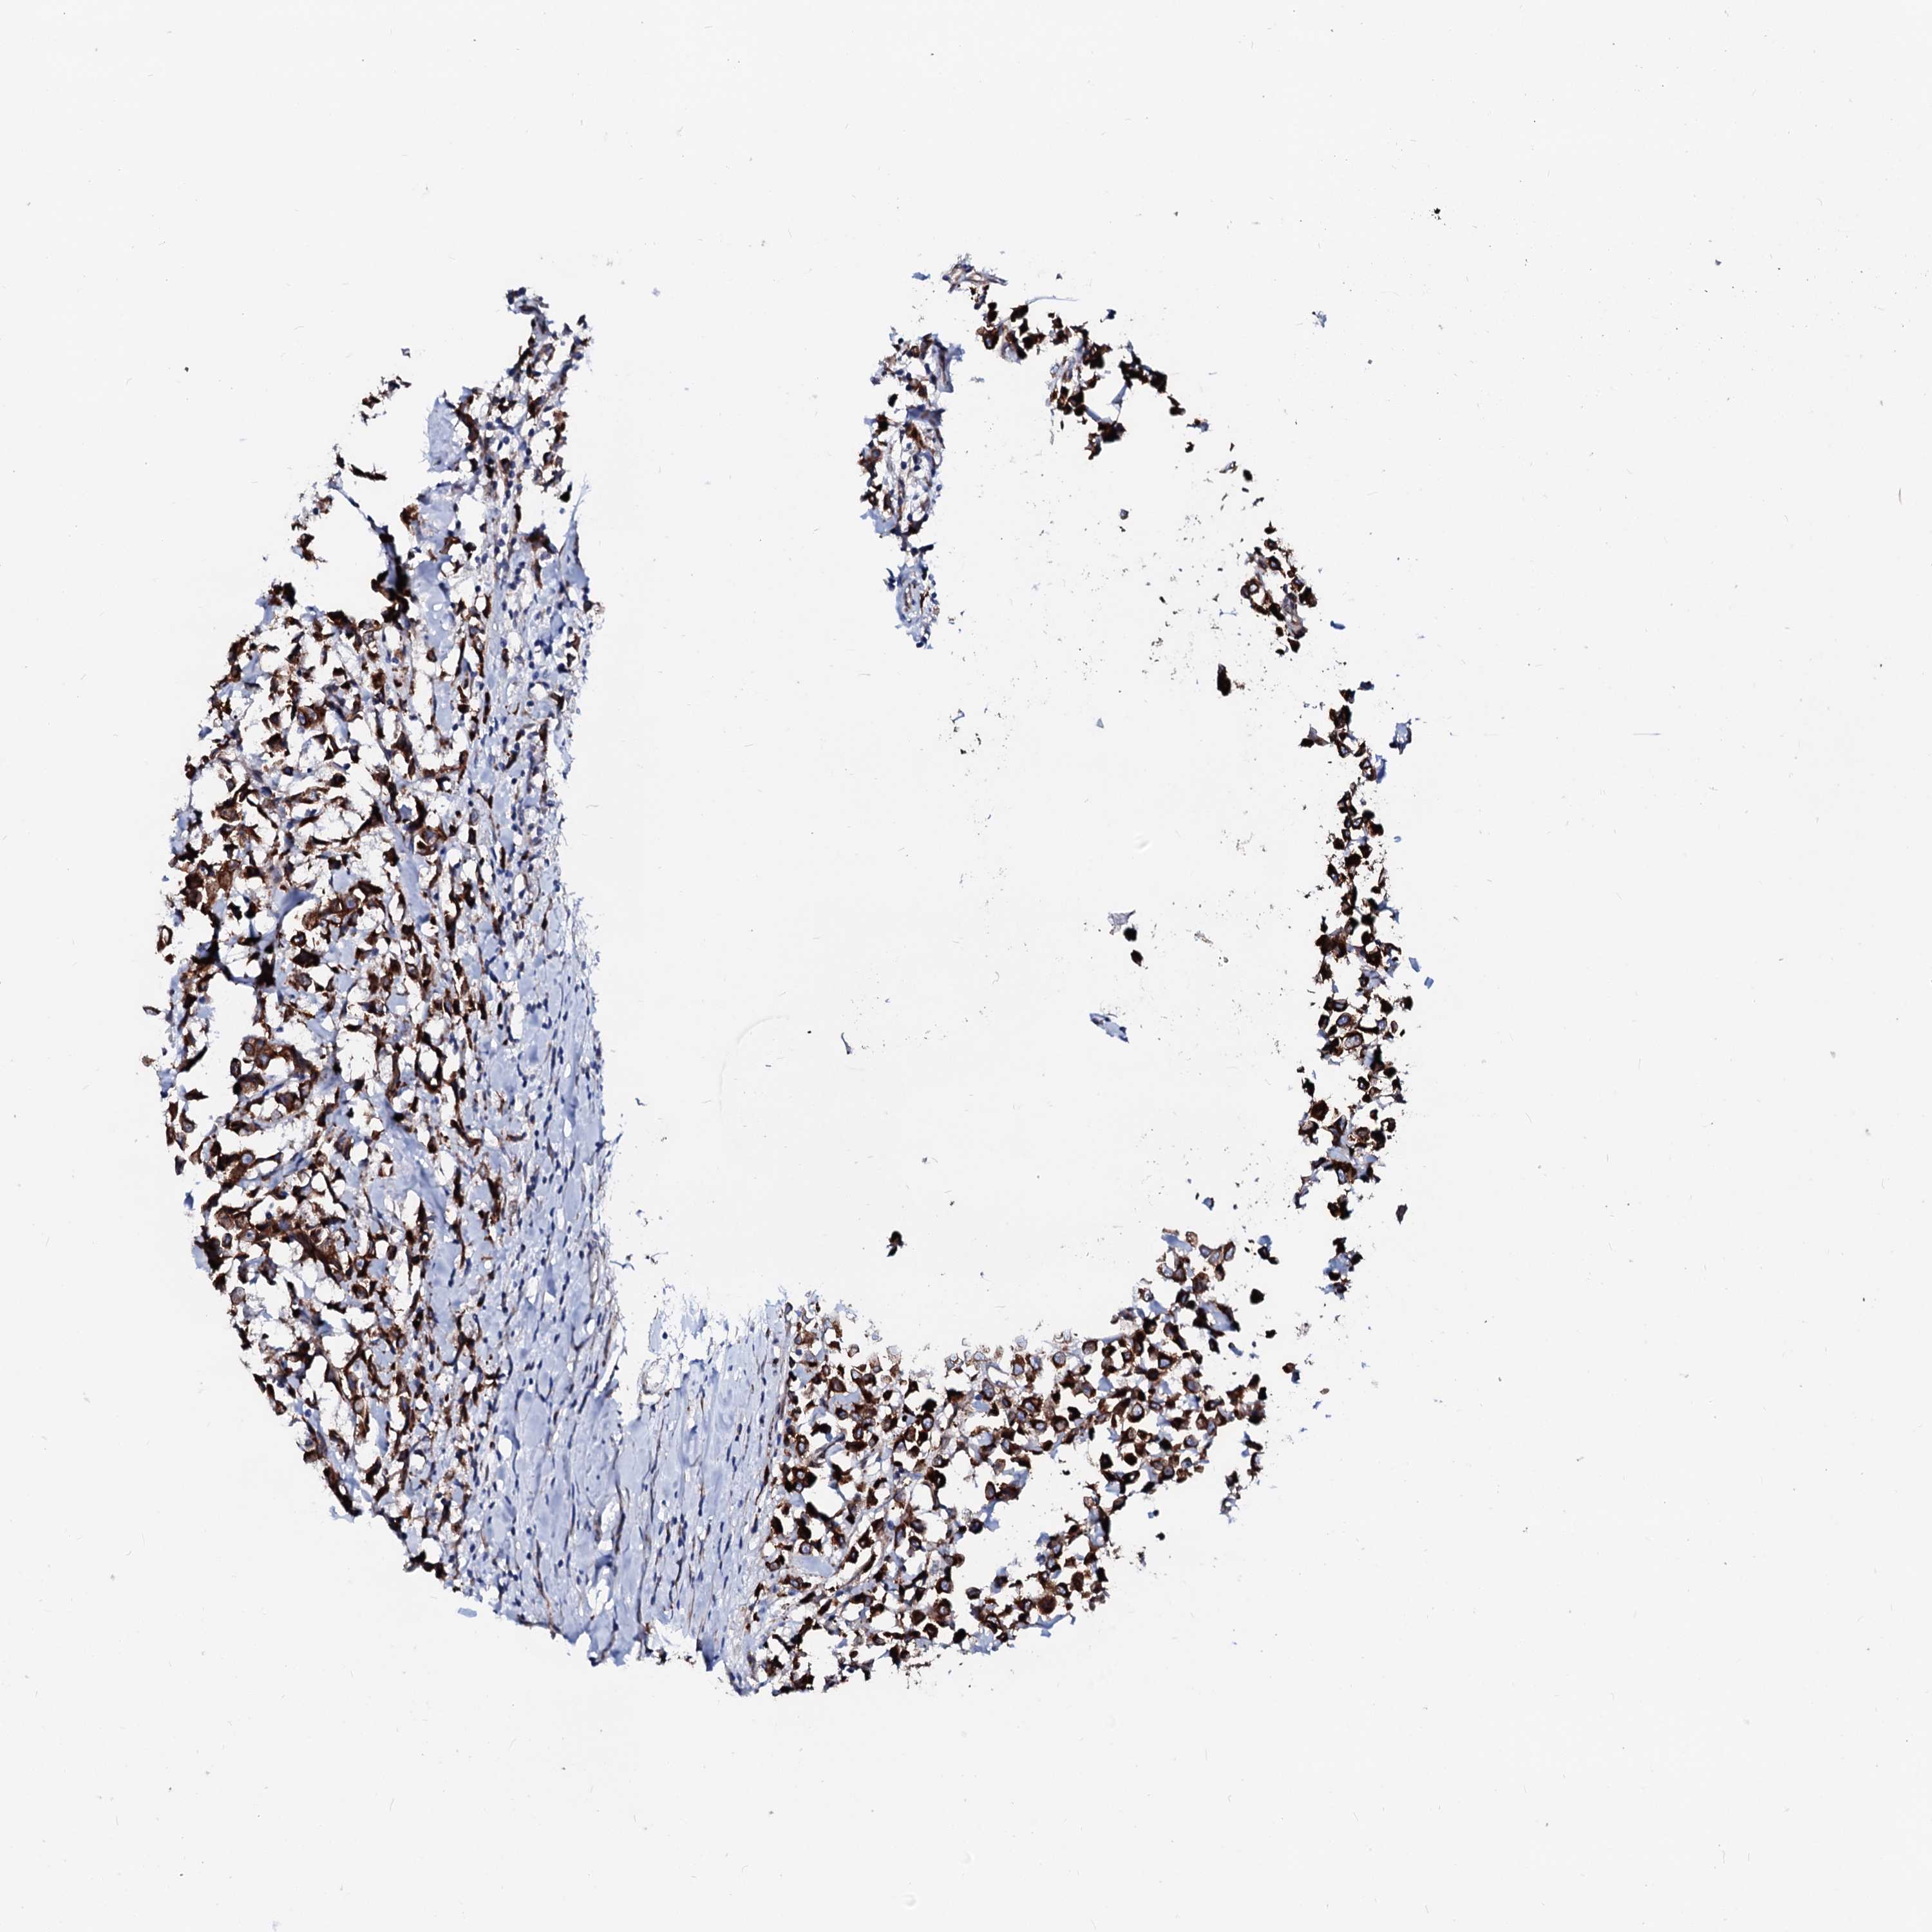

CANCER BREAST CANCER Show tissue menu

BRCA TCGA BRCA VALIDATION PROTEIN EXPRESSION